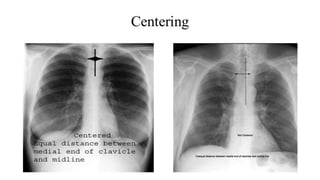

Rotation

• Patient rotation can be assessed by observing the clavicular heads

and determining whether they are equal distance from the spinous

processes of the thoracic vertebral bodies.